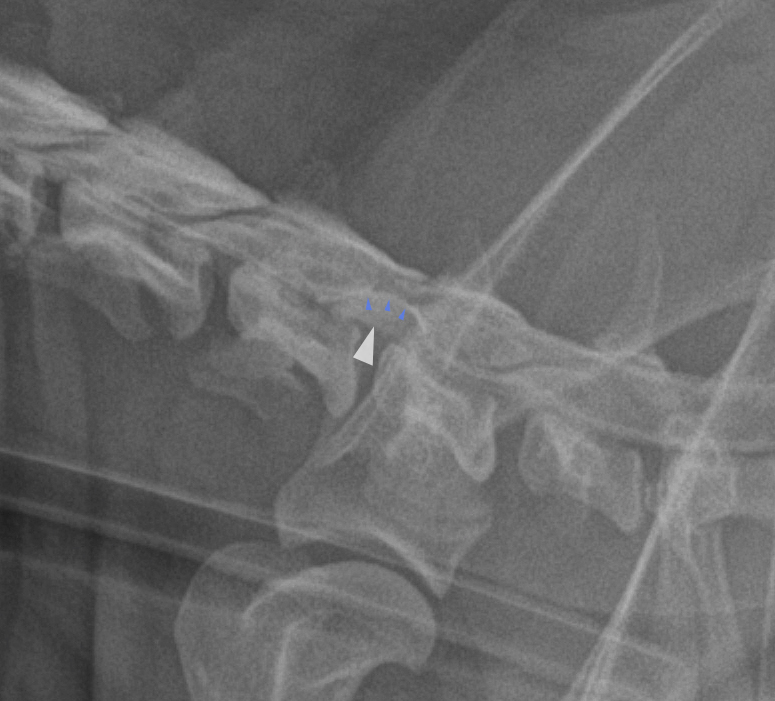

A cysternal myelography was performed, because a cervical compression was suspected.

The lateral myelograms revealed good contrast flow through the cervical area, but a ventral “double column” sign was visible at C5-C6. There was mild widening of the “myelon" at C5-C6 space on the ventrodorsal view and mild contrast thinning on the right.